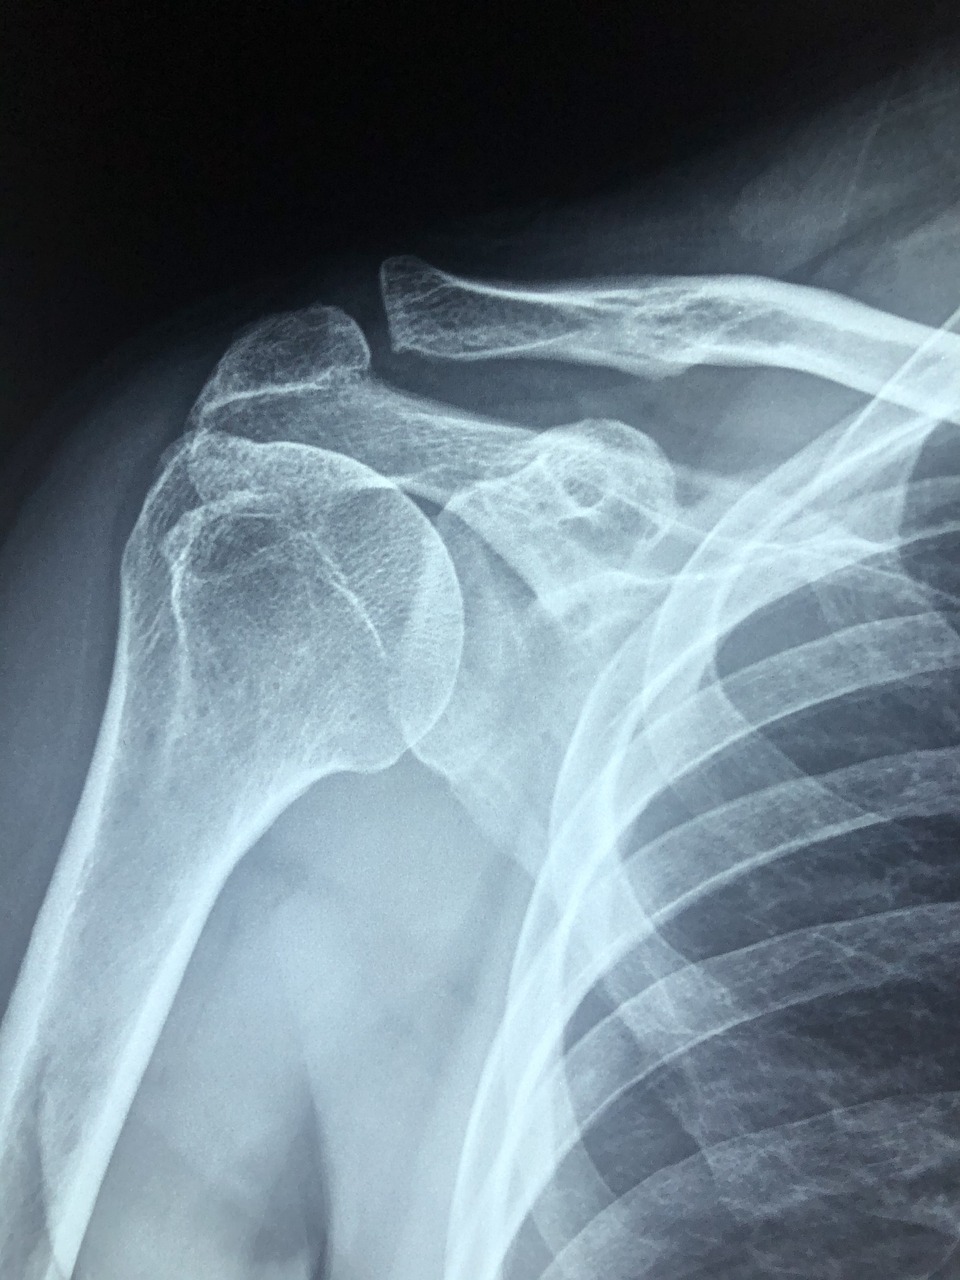

체외충격파 치료(ESWT)는 몸 바깥에서 충격파를 주어, 손상된 조직을 자극하고 자가 회복을 유도하는 방식의 비수술 치료법입니다. 주로 근골격계 질환에 적용되며, 시술 시간은 약 10~15분 정도로 짧고 마취나 입원이 필요 없다는 장점이 있습니다.

특히 어깨 회전근개파열 초기나 석회성 건염, 오십견 등 만성 염증성 질환에 많이 사용되며, 일상생활에 큰 부담 없이 통증 개선 효과를 볼 수 있어 최근 더욱 주목받고 있어요.

보통은 초음파나 MRI 등으로 병변의 위치를 확인한 후 치료에 들어가며, 근육의 혈류 개선과 세포 재생을 촉진해 통증 완화뿐 아니라 운동 범위 회복에도 도움을 줍니다.